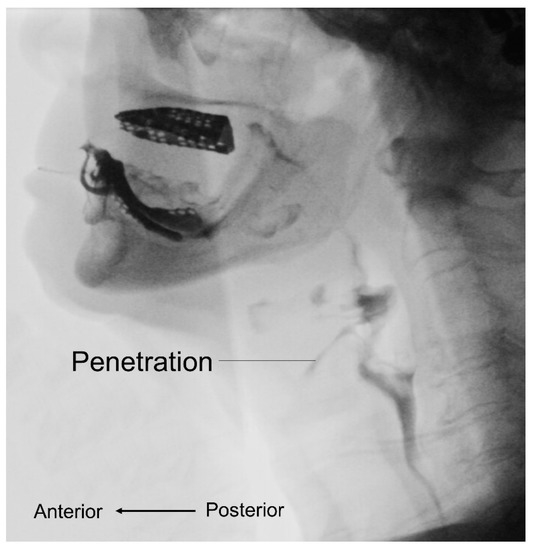

3.3. Videofluoroscopic Swallow Study

- Miyashita, T.; Kikutani, T.; Nagashima, K.; Igarashi, K.; Tamura, F. The effects of sarcopenic dysphagia on the dynamics of swallowing organs observed on videofluoroscopic swallowing studies. J. Oral Rehabil. 2020, 47, 584–590. [Google Scholar] [CrossRef]

- Nakayama, E.; Tohara, H.; Sato, M.; Hino, H.; Sakai, M.; Nagashima, Y.; Kimura, M.; Watanabe, M.; Ooshima, M. Time Course and Recovery of the Movements of Hyoid Bone and Thyroid Cartilage During Swallowing in a Patient With Sarcopenic Dysphagia. Am. J. Phys. Med. Rehabil. 2020, 99, e64–e67. [Google Scholar] [CrossRef]